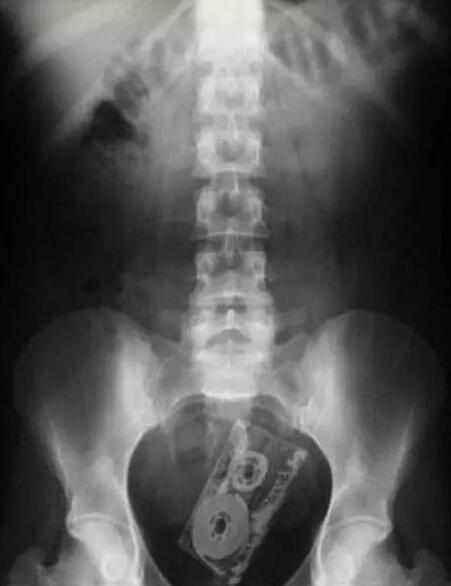

手机不够了,录音带也可以